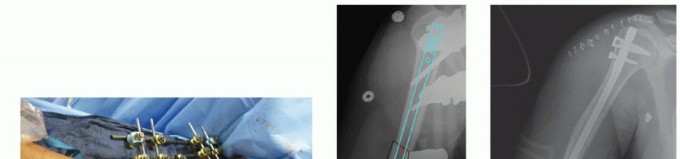

DEFINITION Fractures involving the proximal region of the humerus that provide the supporting framework for t…